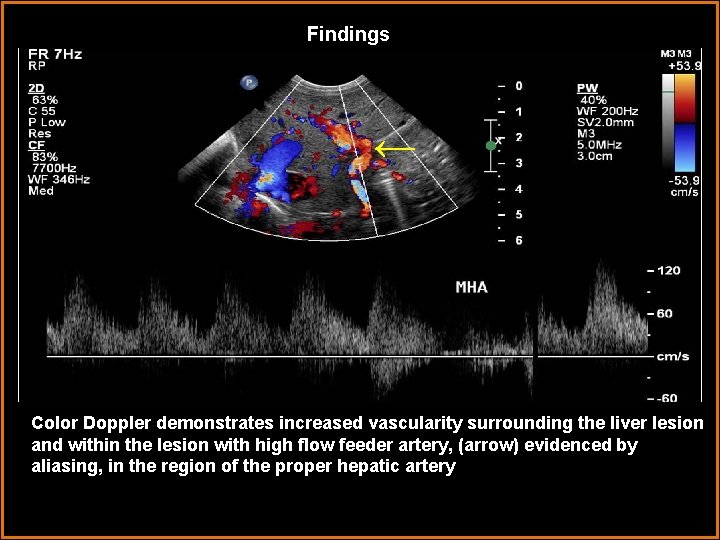

Findings ← Color Doppler demonstrates increased vascularity surrounding the liver lesion and within the lesion with high flow, evidenced by aliasing (arrow), in the region of the proper hepatic artery. High flow is noted predominantly within the periphery of the lesion. There is absence of flow within the center of the lesion consistent with thrombosed vasculature

Findings ← Color Doppler demonstrates increased vascularity surrounding the liver lesion and within the lesion with high flow feeder artery, (arrow) evidenced by aliasing, in the region of the proper hepatic artery